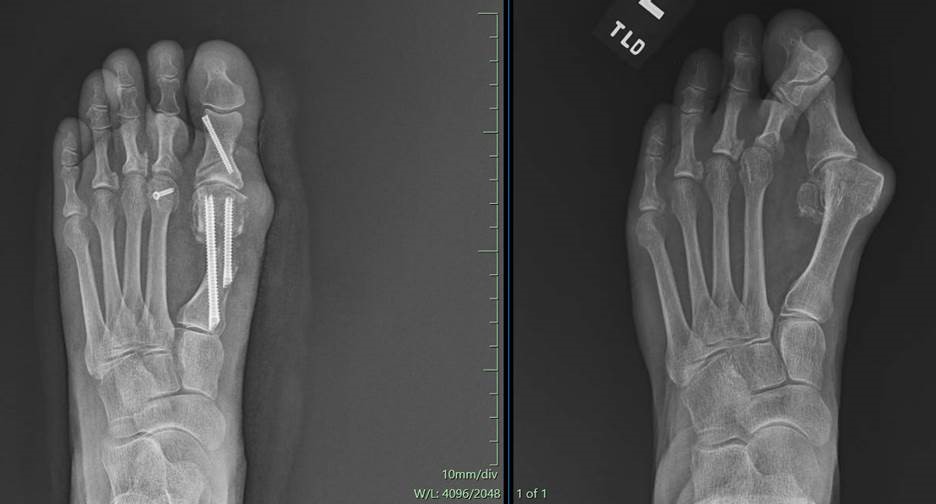

Before and After Surgery

Podiatry